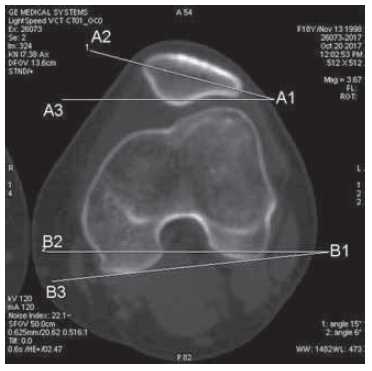

True anteversion (retroversion) of the femoral neck

Two sections were used: one section through the distal segment of the femur (as in the measurement of the TT–TG index), and, accordingly, a line was drawn through the posterior edges of the femoral condyles (B1–B3) (Fig. 3b); the second section was made through the femoral neck, and a line was drawn through the center of the head and neck of the femur (A1–A2) (Fig. 3a). The angle between the two lines represents the cervical anteversion. According to Murphy, in patients with patellar instability this parameter is 15.6 ± 9°, in patients without instability it is 10.8 ± 8.7° [16]. However, the values of both groups overlap, and the threshold value is not determined statistically significantly. Our data, as well as other data in the literature [17] indicate that a value of more than 30° is an important factor leading to posttraumatic patellar instability. Consequently, these patients require surgical correction of the femoral deformity, such as corrective supracondylar osteotomy.

Fig. 3. Measurement of the true antterissia (retroversion) of the femoral neck